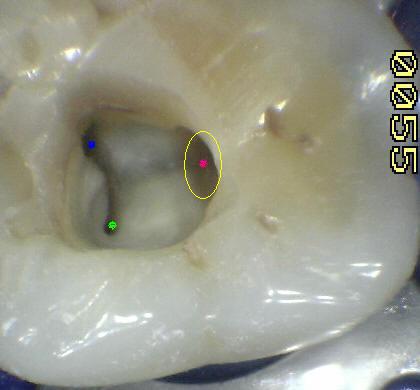

La flecha amarilla indica un posible cuarto conducto. Debe abrir hacia mesial  para eliminar la pared marcada en un circulo celeste, a la misma profundidad que el conducto mesio-vestibular.  Ver imagen derecha.

El conducto y el orificio es esencialmente un agujero en la raíz, la transmisión de luz  muestra al orificio de entrada del conducto como una mancha oscura en un fondo brillante. Ver imagen izquierda superior, la siguiente imagen es el resultado de utilizar una cámara intraoral, con 10 aumentos (X10)

El poder de magnificación del MO con visión indirecta y luz coaxial permite localizar las entradas de los conductos calcificados. Incluso los más pequeños y difíciles de ver como el conducto mesio-palatino (Ver flecha amarilla imagen superior izquierda)

Observe en la imagen superior la dentina secundaria de color blanca que obstruye la entrada de los conductos. Imagen X10 cámara intraoral.

Tres conductos en piso de cámara pulpar, el conducto distal se encuentra ensanchado en sentido buco-lingual, debe sospechar la existencia de dos conductos que comparten el orificio de entrada. Cámara intraoral X10 aumentos.

1º Molar inferior: El orificio de entrada del conducto distal se encuentra ensanchado en sentido buco lingual, debe sospechar la existencia de un cuarto conducto.

La localización  de un cuarto conducto se lleva a cabo con la técnica radiológica de Clark o por medio de una lima curvada en distal para sondear la pared lingual ó vestibular del conducto distal. Imagen inferior

DS: dentina secundaria de color más claro. Cámara intraoral X10 aumentos.